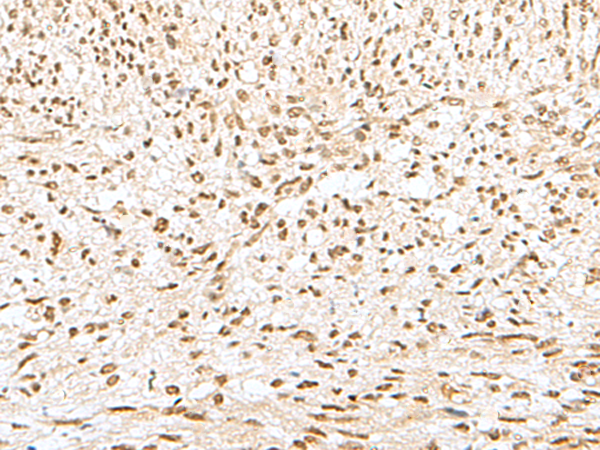

ELISA, IHC

IHC positive control:

Human liver cancer and Human tonsil

IHC Recommend dilution:

30-150